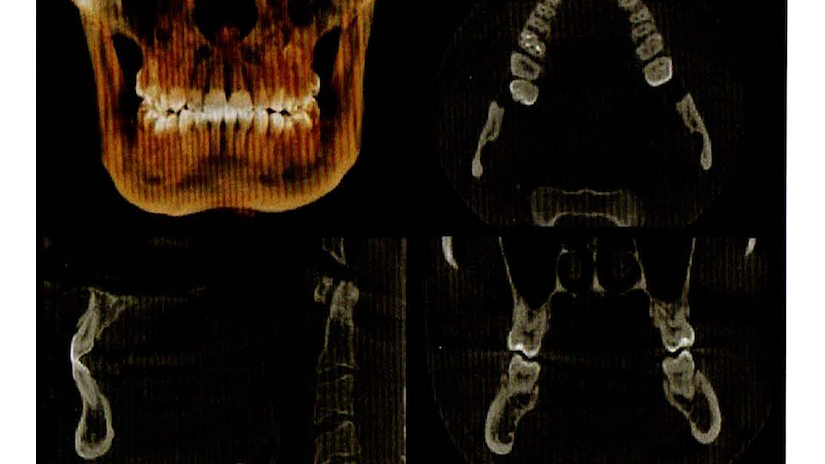

CT撮影(3次元画像の撮影)

🩺 特徴

・顎の骨や歯を立体的(3D)に撮影可能

・インプラントや親知らずの抜歯、顎関節症の診断に最適

・詳細な骨の厚みや神経の位置を正確に把握できる

😊 患者さんにとってのメリット

✔ 精密な診断ができるので、より安全な治療計画を立てられる

✔ 手術のリスクを最小限に抑えられる

✔ 顎関節症の原因を詳しく調べられる

💡 こんなときに役立ちます!

・インプラント治療を検討している方

・親知らずの抜歯が必要な方

・顎関節症や外傷の診断